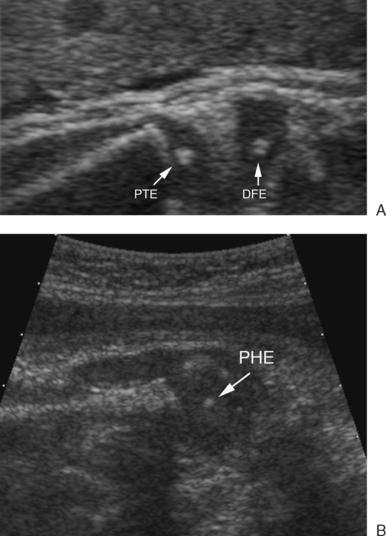

The Fetal Musculoskeletal System